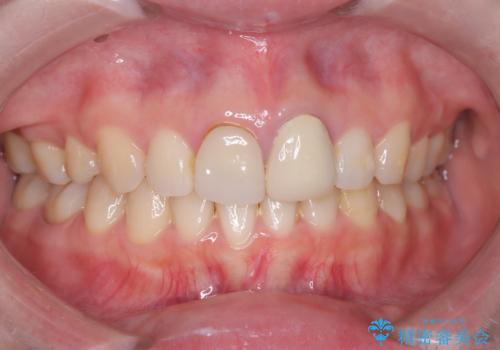

- 以前他院で治療した前歯の被せものの見た目の不満を主訴にご来院されました。レントゲンと診査の結果、被せものの不適合だけでなく、その土台となる歯の根管充填(根の治療の詰め物)が不十分であることが判明。再感染のリスクを避けるため、まず精密根管治療を行い、その後に最も審美性に優れたオールセラミッククラウンで修復する治療計画を立案しました。これにより、見た目の改善と歯の寿命の長期化を目指しました。

治療は、再感染の原因となっていた粗な根管充填材を丁寧に取り除く精密根管治療から開始しました。治療中はラバーダムと歯科用顕微鏡を使用し、根管内を徹底的に清掃・消毒。根の先まで緊密に薬を詰めることで、再発リスクを最小限に抑えました。根管治療の完了後、歯ぐきの状態を整え、周囲の歯と調和するオールセラミッククラウンを作製。金属を一切使わないため、透明感のある自然な仕上がりとなり、長年の見た目のコンプレックスも解消。歯の内部から表面までを根本的に改善することができました。